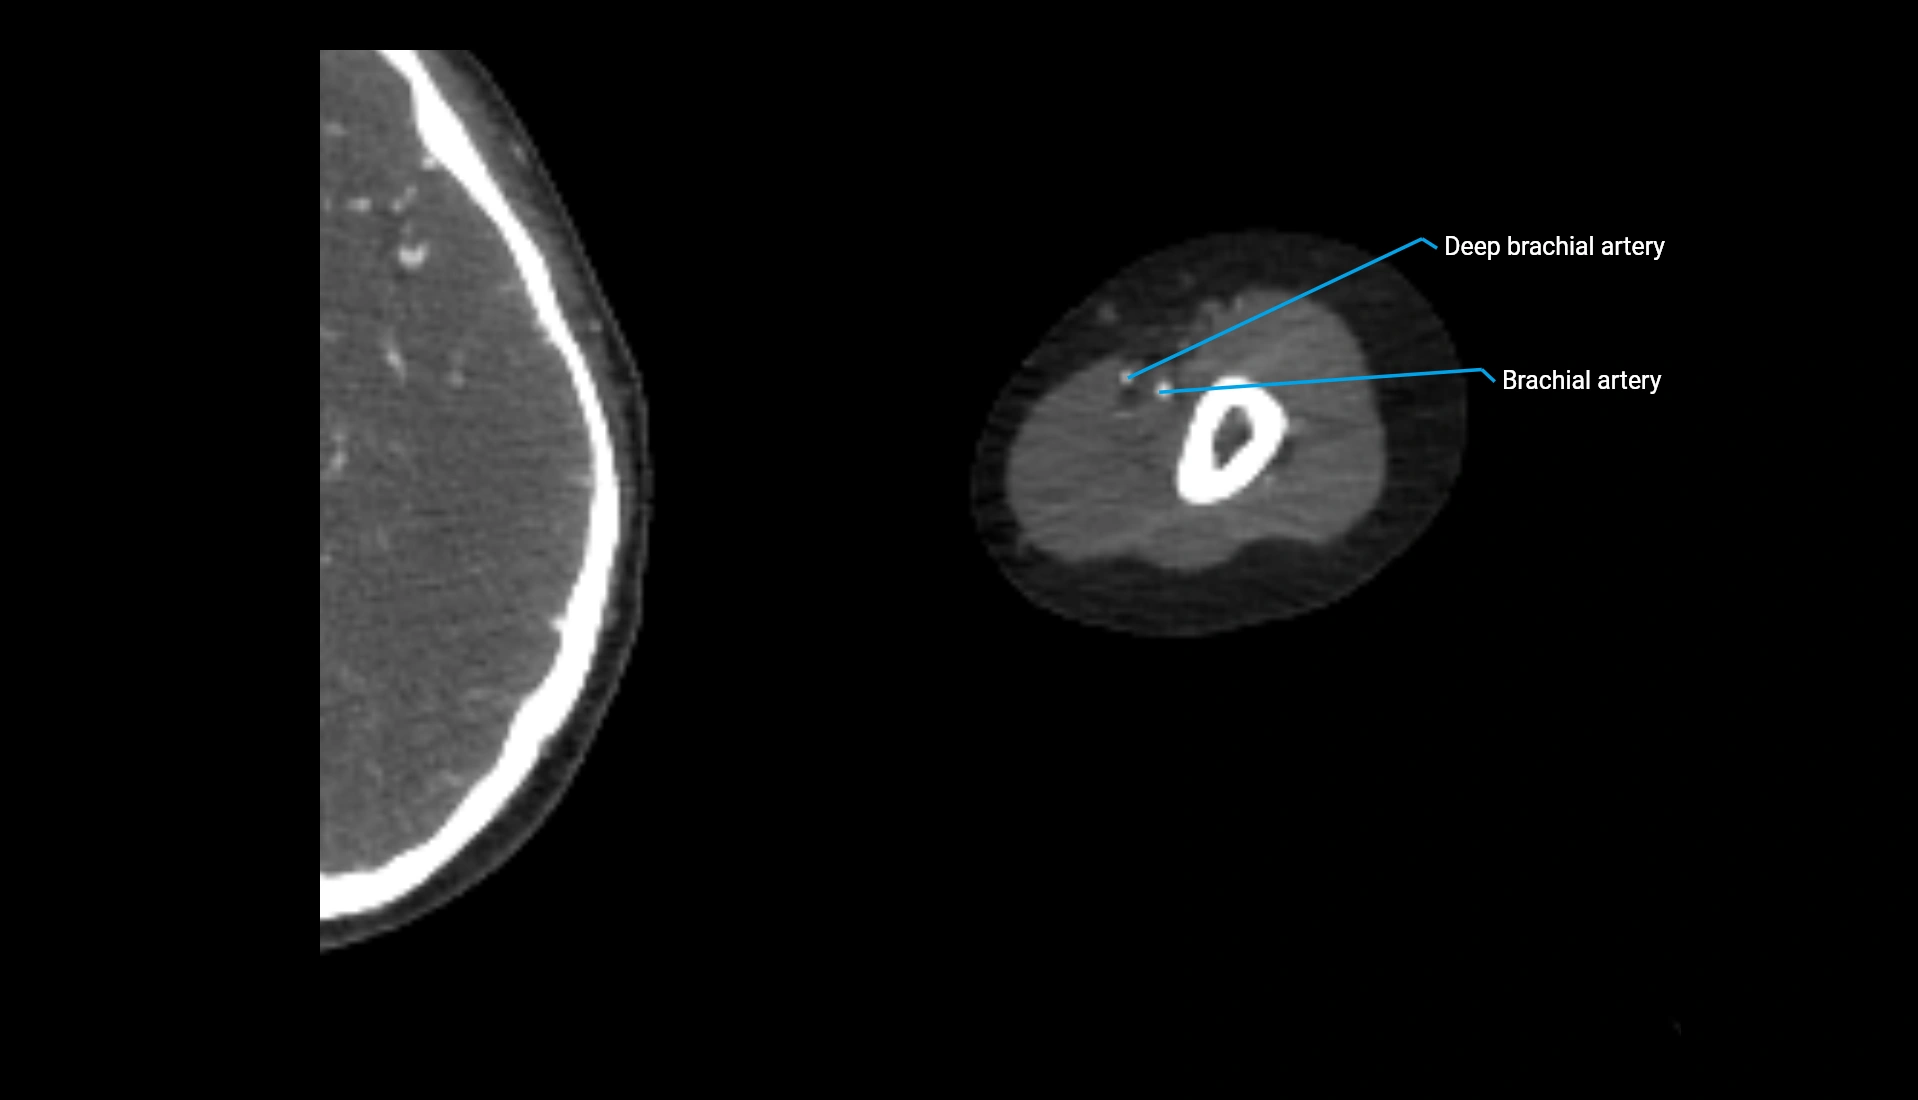

CT Appearance

Non-Contrast CT:

• Cortex: High-density, sharply defined

• Subchondral bone: Dense cancellous matrix

• Articular surface: Smooth concave contour articulating with the capitellum

• Excellent for evaluating bone integrity, alignment, and subtle fractures

Post-Contrast CT:

• Bone: No enhancement

• Joint capsule and synovium: Mild enhancement outlining the joint

• Improves contrast between soft tissues and bony margins

• Useful in detecting subtle joint abnormalities or postoperative changes